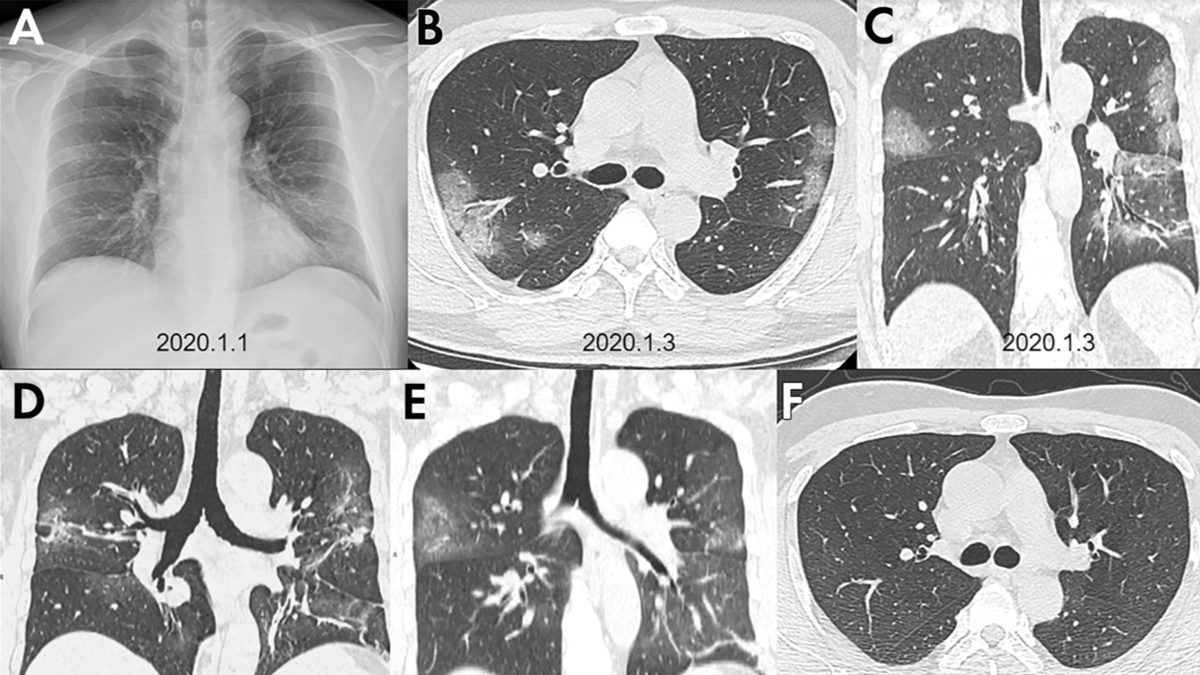

A larger area of lung involvement was consistent in the patients that had passed away.